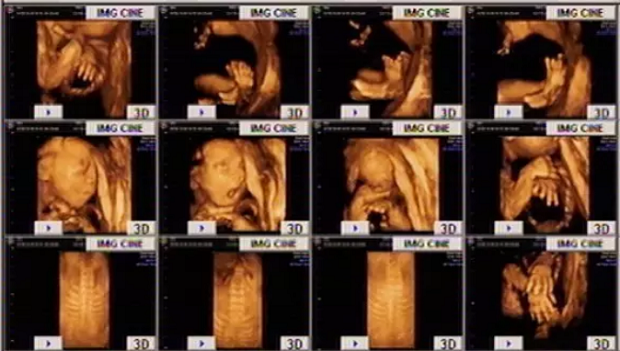

做四维彩超必须要保持检查室的安静:这一点最重要。每一个孕妇都希望得到非常准确的检查,以便了解到胎儿发育的各种情况,这个也是对社会和家庭的负责,所以孕妇必须保持安静以配合我的这次检查。为了保持我们检查室的安静,在检查的时候我们会给孕妇讲,在检查的时候不要讲话、不要笑、不要动、还要把手机关掉,很多人都不理解。你和你的胎儿已经相处了几个月了,你的声音、你手机的声音、你的笑声和你的动作他都非常熟悉,而且胎儿还会配合你的动作、声音、手机的声音、笑声做出相应的回应。这样胎儿的动作变化太大,就会严重影响到我们检查的准确性,更加影响我们做的图像质量的清晰度,可能因为你的这个小动作你就有可能要去运动几个小时才能看得完,来达到我们需要检查的目的。因此如果你能安静的配合我的检查,我的检查就会又快又好,每一个切面做的就非常标准,图像的清晰度也非常高,达到我们想要的目的。